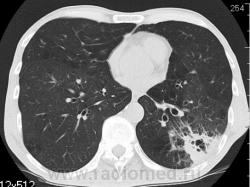

КТ - ОГК.  Ваше мнение коллеги?

На фоне консолидации полость без содержимого. Может быть всё что угодно, что сопровождается деструкцией. Нужны ещё томограммы в лёгочном окне.

Изображения выставлены все. Ваше мнение уважаемые коллеги?

Туберкулёз.

Туберкулёз?